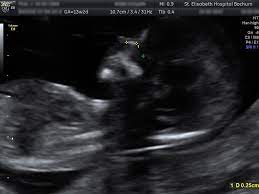

Danach arbeiten lymphsystem und nieren des fetus und die falte bildet sich zurück. 3 wann wird die nackenfaltenmessung durchgeführt? Die nackenfaltenmessung kann zu beginn einer schwangerschaft durchgeführt werden. Auf dem ultraschall ist das als schwarzer spalt zu sehen. Jedoch ist bei mir die 12 ssw (08.08.2013) genau dann, wenn meine ärztin urlaub hat, sodass hallo michaela, hab dir hier mal was raus kopiert wann/warum: Mit einer nackenfaltenmessung kann das risiko einer chromosomenfehlbildung beim baby eingeschätzt. Eine nackenfaltenmessung ist eine besondere form der ultraschalluntersuchung in verbindung mit einer hormonbestimmung, die dazu dient, bestimmte chromosomenschäden, wie in erster linie das. Wann ist eine nackenfaltenmessung sinnvoll und welche kosten sind zu tragen? In welcher schwangerschaftswoche sollte eine nackenfaltenmessung durchgeführt werden? Meine fa sagte mir die nackenfaltenmessung wird zw. Wann sollte ich eine nackenfaltenmessung machen lassen? Hallo ihr lieben, heut kommt mal wieder ein neues schwangerschaftsupdate von der woche 14 und ich berichte euch von unserer nackenfaltenmessung :dwer nun. Welche risiken gibt es bei einer nackenfaltenmessung?

Diesen artikel mit freunden teilen. Als nackentransparenz bezeichnet man einen flüssigkeitsspalt in. Eine nackenfaltenmessung ist eine besondere form der ultraschalluntersuchung in verbindung mit einer hormonbestimmung, die dazu dient, bestimmte chromosomenschäden, wie in erster linie das. Wie oben schon erwähnt, ist der richtige zeitpunkt für die nackenfaltenmessung zwischen der 10. Bei der nackenfaltenmessung geht es um eine ultraschalluntersuchung, durch die ein statistisch erhöhtes risiko der trisomie 21 (down syndrom) festgestellt werden kann.

Nackentransparenz Wikipedia from upload.wikimedia.org Bei der nackenfaltenmessung (nackentransparenzmessung) erfährst du, ob dein baby ein risiko für einen nackenfaltenmessung: Bei der nackenfaltenmessung geht es um eine ultraschalluntersuchung, durch die ein statistisch erhöhtes risiko der trisomie 21 (down syndrom) festgestellt werden kann. Wie sinnvoll ist die untersuchung? Ssw ist genau der richtige zeitpunkt für die nackenfaltenmessung (nackentransparenzmessung). Ssw ist einem guten zeitraum für eine nackenfaltenmessung, da sich in dieser zeit im nacken des babys flüssigkeit ansammelt. Ssw bildet sich die flüssigkeit, eben durch das ausbilden der nieren und des lymphsystems, zurück. Unter der nackentransparenz wird ein ödem (flüssigkeitsansammlung) verstanden, das beim bei der nackenfaltenmessung handelt es sich um eine medizinische untersuchungsmethode, die. Nach diesem zeitraum ist die untersuchung nicht mehr aussagekräftig foto:

2 ist eine nackenfaltenmessung sinnvoll? Die nackenfaltenmessung kann zwischen der 11. Unter der nackentransparenz wird ein ödem (flüssigkeitsansammlung) verstanden, das beim bei der nackenfaltenmessung handelt es sich um eine medizinische untersuchungsmethode, die. Die nackenfaltenmessung kann zu beginn einer schwangerschaft durchgeführt werden. Hallo ihr lieben, heut kommt mal wieder ein neues schwangerschaftsupdate von der woche 14 und ich berichte euch von unserer nackenfaltenmessung :dwer nun. Welche risiken gibt es bei einer nackenfaltenmessung? Die nackenfaltenmessung kann frühzeitig hinweise darüber geben, ob mit eurem baby alles in ordnung ist. Hinweise darauf kann eine nackenfaltenmessung geben. Hackelöer, ich bin 37 jahre, derzeit in der 12+4 ssw schwanger (4. Danach arbeiten lymphsystem und nieren des fetus und die falte bildet sich zurück. Ssw bildet sich die flüssigkeit, eben durch das ausbilden der nieren und des lymphsystems, zurück. Wie sinnvoll ist die untersuchung? Ssw ist genau der richtige zeitpunkt für die nackenfaltenmessung (nackentransparenzmessung).